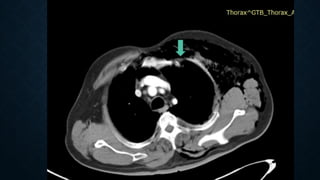

PNEUMOMEDIASTINUM

• Usually from ruptured alveoli

• Can also be from trachea, bronchi,

esophagus, bowel and neck injuries

SIGNS

• Linear paratracheal lucencies

• Air along heart border

• “V” sign at aortic-diaphragm

junction

• Continuous diaphragm sign

PNEUMOMEDIASTINUM • Usually fromruptured alveoli • Can also be from trachea, bronchi, esophagus, bowel and neck injuries

SIGNS • Linear paratracheallucencies • Air along heart border • “V” sign at aortic-diaphragm junction • Continuous diaphragm sign